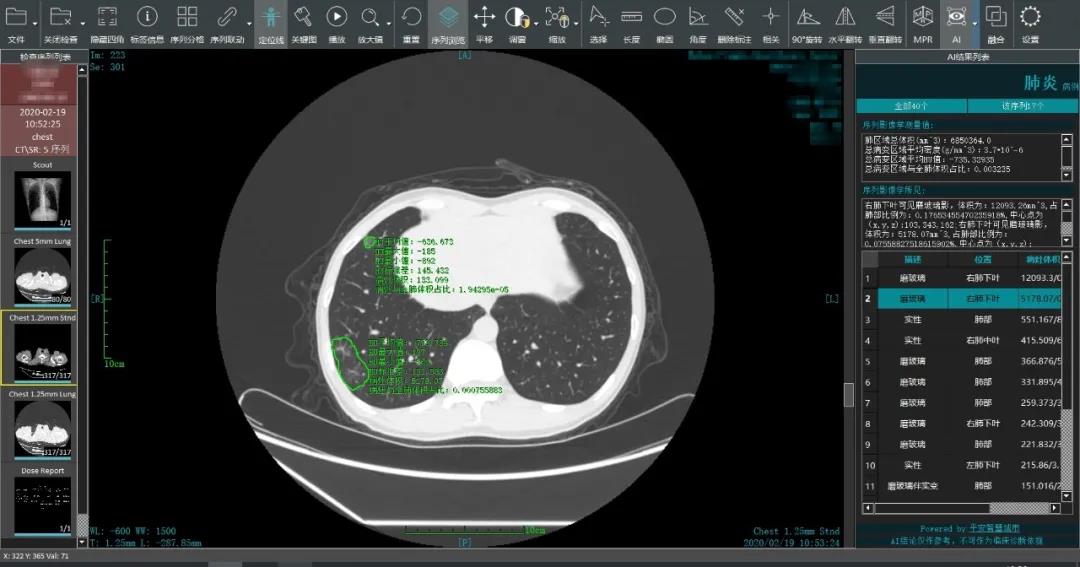

以医疗系统为例,每次重大疫情期间医疗资源都极度匮乏。但抗击新冠肺炎疫情期间不少科技企业的加入让这一困境有所好转。以平安智慧城市的新冠肺炎CT阅片为例,通过人工智能技术能助力医生将传统阅片时间从15分钟缩短至15秒,累计阅片数超400万张,筛选出超2万名疑似患者。